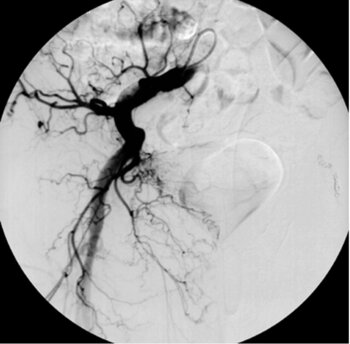

Fallbeispiele Leber – TACE (TransArterielle ChemoEmbolisation) der Leber

Digitale Subtraktionsangiografie: In der Leber zeigen sich multiple pathologische Anreicherungen, die Tochtergeschwülsten eines Karzinoids entsprechen.

Digitale Subtraktionsangiografie: Einen Monat nach der erfolgten Chemoembolisation, bei der direkt in die Leberarterie ein Medikament zur Tumorbehandlung gegeben wurde (TACE), stellen sich die zuvor zahlreichen Metastasen nicht mehr dar.